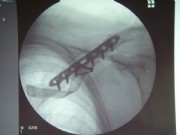

Acromioclavicular dislocation

(Acromioclavicularluxation)

By falling on the arm, the joint capsule of the so-called acromio clavicular joint (between acromion and clavicle) tear, and the clavicle height, depending on the severity of the injury, moves more or less. Lower stages (called Tossy I and II) are not operated, but eventually stabilized with a shoulder brace.

The Tossy III is a complete dislocation (tearing of the capsule ligament entirely) and should at least be surgerically treated in case of younger patients. This is done with a plastic band loop, which is looped around the coracoid and which brings the clavicle back to its original position. This band is fixed by means of clamping screws.

The arrow points to the here already repositioned acromioclavicular.